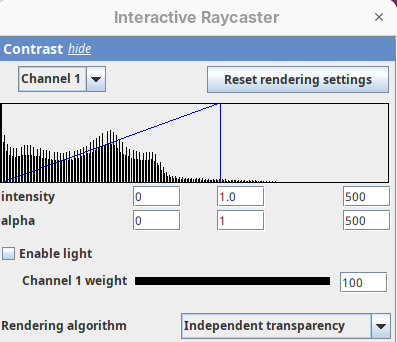

Contrast

The Contrast section shows a histogram of pixel intensities of the image for each channel, which we can choose using the dropdown menu. We can set the minimum, gamma, and maximum values for the intensity and alpha (transparency) properties of each pixel. The weight option controls the general opacity of the channel (0=invisible, 100=visible). There’s also more advanced options like lighting and rendering algorithm which we’ll simply use the default states as they are usually good for most use cases.

Adjusting the intensity and alpha values is the most impactful way to improve the 3D rendering. With the intensity setting we can define which pixel value in the image corresponds to total black (minimum) and which corresponds to total white. It’s the same as in the standard Brightness & Contrast tool. By default, 3Dscript will load these values from the original stack. In this case, it loaded min=3 and max=521.

Note that when you change an intensity value, the min/max black line in the histogram moves. You can also grab the line and move it manually to change the values.

The blue line represents the alpha values. In 3D rendering, a pixel has a transparency value linked to its intensity. The alpha min defines the value for full transparency and the max the value for full opacity.

By default 3Dscript sets the gamma value of alpha to 2.0. That’s a good default for fluorescence microscopy (see the next dataset below), but since this is MRI data, we need to tweak it a little differently.

- Set the alpha gamma value to

1.0.

Note that this improves the visualization as the head’s surface becomes better visible.

maxback to500.

Generally, setting the intensity and alpha to the same values is a good starting point for optimizing the rendering.